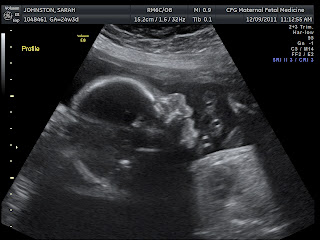

We got a sneak peak at the little one due this March 28th! We are happy to report that it has ten fingers, ten toes and there is only one!! Everything looks to be as it should! We are keeping it a mystery as to whether this little one will wear pink or blue! So start your baby pools! Only fifteen weeks to go!

This one is getting ready to come out feet first... just like his or her sister!

This little one looks a lot like Norah did at her ultrasound!